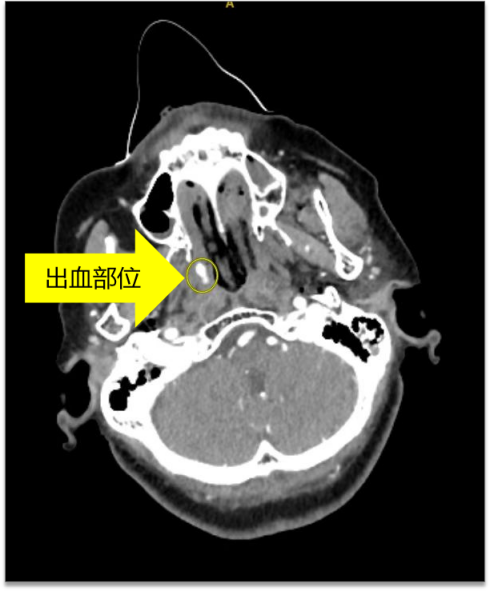

结合头面部增强CT检查

判断为面部骨折导致的血管破裂

进而引起大出血

证实因面部骨折创伤

引起的周围小血管破裂